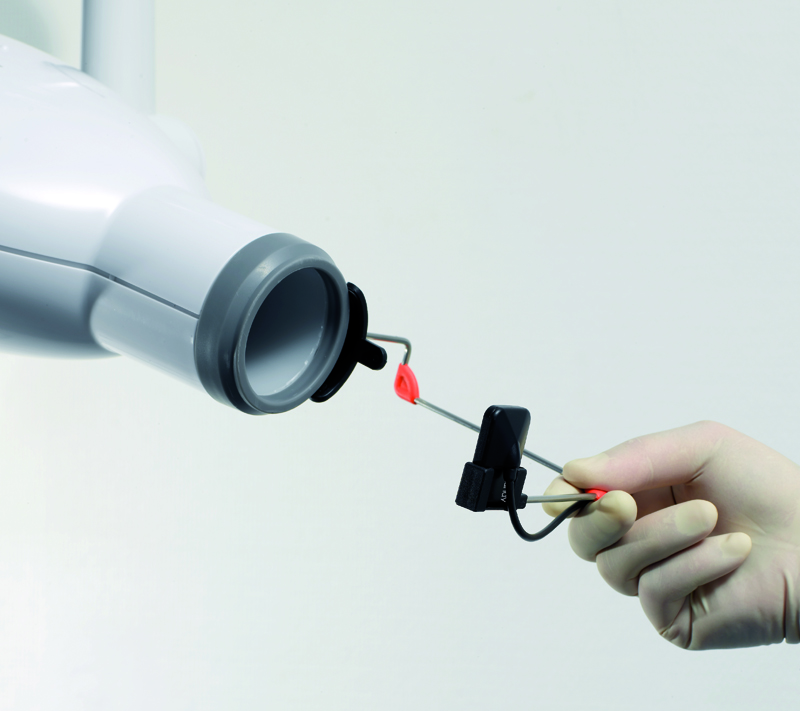

سنسور هوشمند با قابلیت Automatic wake-up و بدون نیاز به فعال سازی دستی

امکان چرخش 360 درجه ای کابل دایرکت USB که در گردنه ی سنسور تقویت شده است

600mm² Sensitive surface Direct USB - without box

3meters cord with medical connector

Repairable cable - IPX 7 waterproof standard

Accessories:

Positioners starting kit, sheets, Wall stand